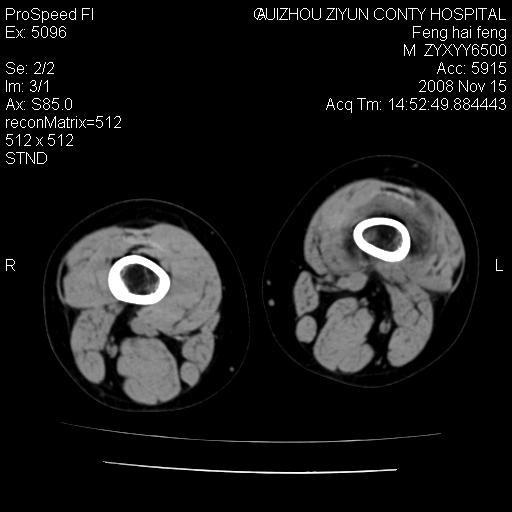

标题: CT16656:M 14Y 左膝关节肿胀一年余。其余病史不详。 [打印本页]

标题: CT16656:M 14Y 左膝关节肿胀一年余。其余病史不详。

考虑左侧髌骨结核;左膝关节滑膜肿胀、增厚,关节囊积液。

左膝滑膜型关节结核可能性大!支持!滑膜型关节结核主要ct表现:关节囊肿胀,积液,关节面见小破坏灶,并见点状死骨!

左膝滑膜型关节结核可能性大!支持!滑膜型关节结核主要ct表现:关节囊肿胀,积液,关节面见小破坏灶,并见点状死骨

好大的左腿!考虑左侧髌骨结核,左膝关节滑膜肿胀、增厚,关节囊积液。

左侧髌骨结核;左膝关节滑膜肿胀、增厚,关节囊积液